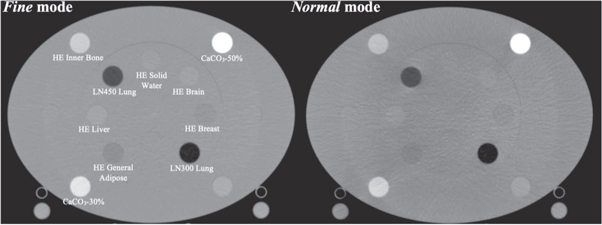

The Gammex electron density phantom (Gammex, Middleton, WI) was utilized for HU-to-physical density calibrations. This phantom was previously used to calibrate the planning CT applied in this study (Siemens SOMATOM Definition Edge, Siemens AG, Munich, Germany) and contains inserts for various tissue-substitute rods with diameters of 28.5 mm. Two phantom configurations are available ('head'−20 cm diameter or 'body'−30 cm height by 40 cm width), and the phantom has a depth in the axial plane of 16.5 cm. In this study, the 'body' configuration was used to acquire the calibration data. Calibration curves for the ClearRT system were acquired with Thorax (120 kVp) anatomy protocols, the X-Large body size (to maximize the mA per view), and a 440 mm FOV for Fine and Normal modes. Note that no calibration curve was acquired for Coarse mode, as the increased beam width and relative decrease in mAs/rotation (due to the decrease in views per rotation) resulted in appreciable artifact in the calibration phantom images regardless of the phantom configuration. Additionally, the manufacturer does not require a calibration for Coarse mode to enable the adaptive radiotherapy function, suggesting that this mode is not recommended/necessary for ART implementation. However, dose calculation was still performed on Coarse mode images for a more comprehensive evaluation in an effort to comment on this accuracy (or lack thereof). Axial image slices of the calibration phantom for ClearRT acquisitions are shown in figure 1. Calibration data for the MVCT system was acquired with Fine mode and a 1 mm reconstruction interval for each reconstruction algorithm. For the ClearRT system, the measured section of the density plug must be at least half a beam width away from the longitudinal ends of the phantom [20]. Thus, analysis of mean CT numbers for the tissue-substitute rods was performed with ImageJ software (National Institutes of Health, US) over a scan extension of ∼10 mm for axial slices in the center of the reconstructed phantom images using regions-of-interest (ROIs) of diameter ∼20 mm placed within the inserts.

Figure 1. Axial image slices of the Gammex electron density phantom used for CT number to physical density calibration in this study. Shown is the 'body' configuration acquired with Thorax anatomy protocols for the ClearRT system for Fine and Normal modes. Inserts are labelled as appropriate.